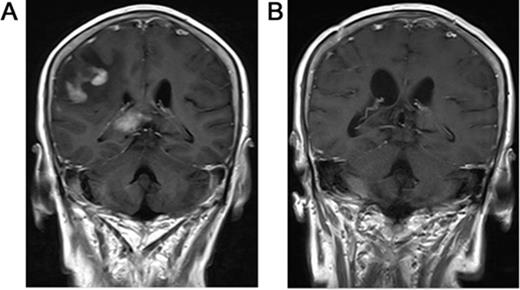

Primary central nervous system lymphoma (PCNSL) is aggressive and confined to the central nervous system, including the brain parenchyma, leptomeninges, spinal cord, eyes or cranial nervous. Morphologically, approximately 95% of these tumors are DLBCL according to the new World Health Organization (WHO) classification. However, PCNSL has treatment outcome distinct from those of systemic DLBCL, as well as dismal prognosis than systemic DLBCL. Our goal was to determine the immunohistochemical profile and prognostic significance for 132 Chinese PCNSL cases. The expression of CD20, CD10, BCL-6, MUM1, CD138, BCL-2, and Ki67 antigens were observed by immunohistochemical method. All cases expressed CD20. CD10, BCL-6, and MUM1 were positive in 15.2% (20/132), 86.4% (114/132), 90.2% (119/132). CD138 was negative in 100% (39/39). BCL-2 was positive in 89.3% (108/121). The Ki67 antigen, a proliferative index, ranging from 1% to 100% (median 85.3%) and 76.5% (101/132) PCNSLs showed Ki67 ≥ 90%. Among 132 cases, 25 (18.9%) were classified as germinal center B-cell-like (GCB); 107 (81.1%) were classified as activated B-cell-like (ABC). The Ki67 index in 25 GCB was similar to that in 107 ABC (p=0.663>0.05). No significant correlation was found between Ki67 index and BCL-2 (p=0.225>0.05). Significant positive correlation was found between Ki67 index and BCL-6 expression (p=.000<0.05). Among 132 cases, 43 had complete data of treatment that received chemotherapy regimens based on HD-MTX. GCB and ABC had similar OS (p=0.969) and PFS (p=0.070). These findings support that PCNSL predominantly express an ABC immunophenotype and express high Ki67 index, and suggest that the proliferative activity of GCB was similar to ABC and the expression of BCL-6 but not BCL-2 was positively correlated with the malignant degree of tumors.